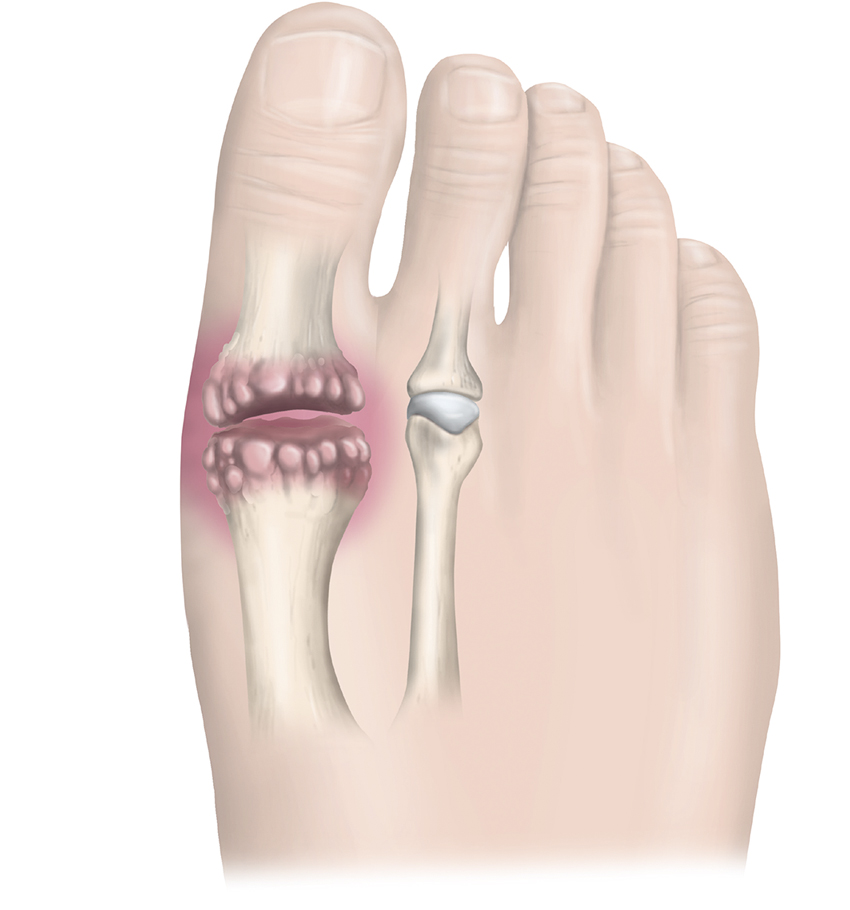

Patient med Mortons metatarsalgi i interdigitalnerv IV. Tillståndet kännetecknas av kompression och förtjockning/svullnad av fotens interdigitalnerver som bland annat kan orsaka neuropatisk, utstrålande smärta.

Hallux rigidus är ett degenerativt tillstånd som engagerar MTP I-leden. Notera erosion av ledbrosket samt tillkomsten av osteofyter kring leden. Detta orsakar som regel reducerat rörelseomfång främst i dorsalflexion.